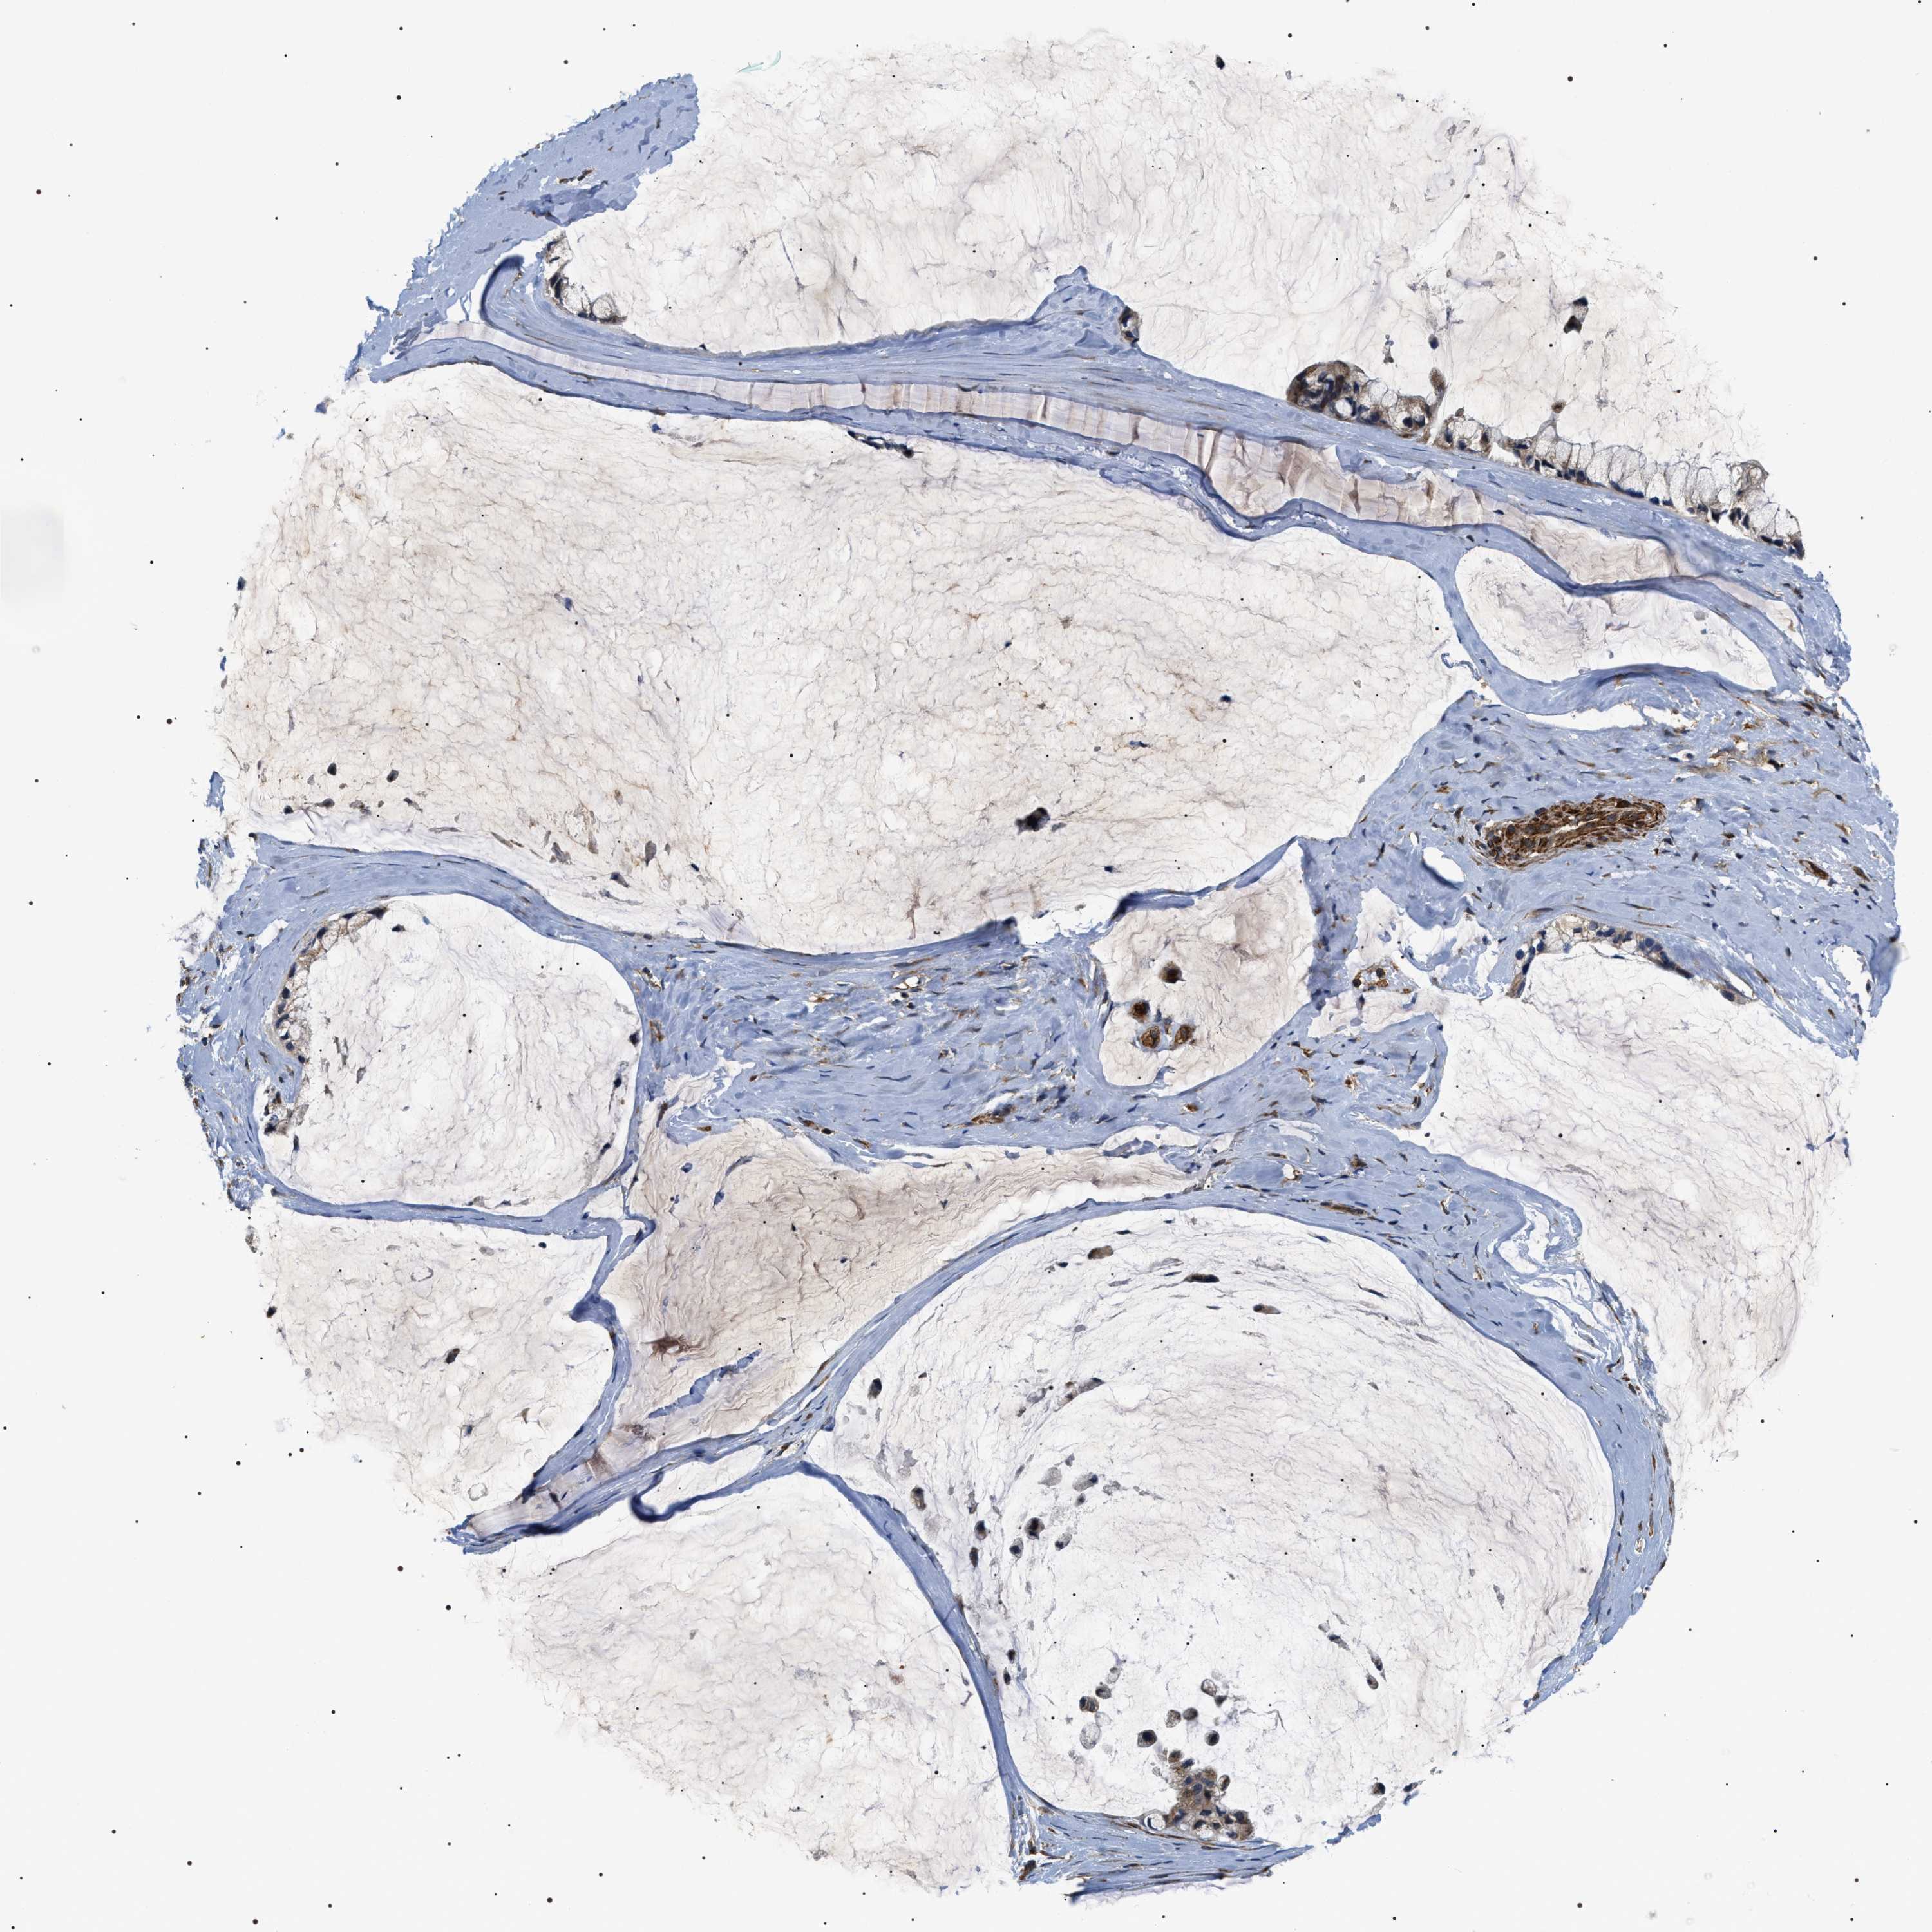

OVARIAN CANCER - Protein expressioni

A mouse-over function shows sample information and annotation data. Click on an image to view it in a full screen mode. Samples can be filtered based on level of antibody staining by selecting one or several of the following categories: high, medium, low and not detected. The assay and annotation is described here.

Note that samples used for immunohistochemistry by the Human Protein Atlas do not correspond to samples in the TCGA dataset.

Antibody stainingi

Antibody staining in the annotated cell types in the current human tissue is reported as not detected, low, medium, or high, based on conventional immunohistochemistry profiling in selected tissues. This score is based on the combination of the staining intensity and fraction of stained cells.

Each image is clickable and will lead to virtual microscopy that enables deeper exploration of all samples and also displays staining intensity scores, fraction scores and subcellular localization as well as patient and tissue information for each sample.

Antibody HPA020386

Staining

High

Medium

Low

Not detected

Intensity

Strong

Moderate

Weak

Negative

Quantity

>75%

75%-25%

<25%

None

Location

Nuclear

Cytoplasmic/membranous

Cytoplasmic/membranous,nuclear

Cystadenocarcinoma, serous, NOS

Carcinoma, endometroid

Cystadenocarcinoma, mucinous, NOS

Carcinoma, NOS